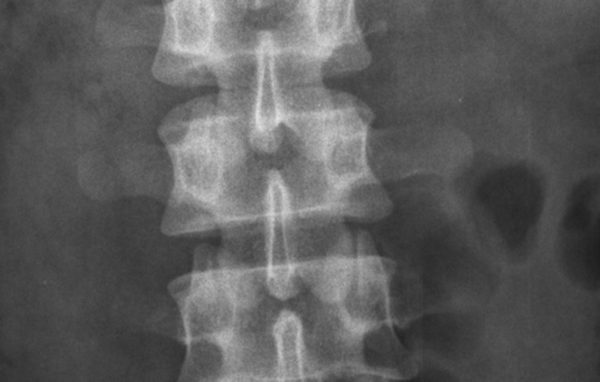

Ca. 500.000 danskere lider af knogleskørhed uden at vide det ifølge Sundhedsstyrelsen. Nu viser en netop afsluttet undersøgelse,…

200.000 danskere er diagnosticeret med knogleskørhed, men området mangler politisk opbakning, mener formand for Osteoporoseforeningen.